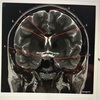

Match 1. Corpus callosum 2. Tentorium 3. Lateral ventricle 4. Thalamus 5. Medulla oblongata 6. 4th ventricle

A. Lateral ventricle B. Corpus callosum C. Thalamus D. Tentorium E. 4th ventricle F. Medulla oblongata